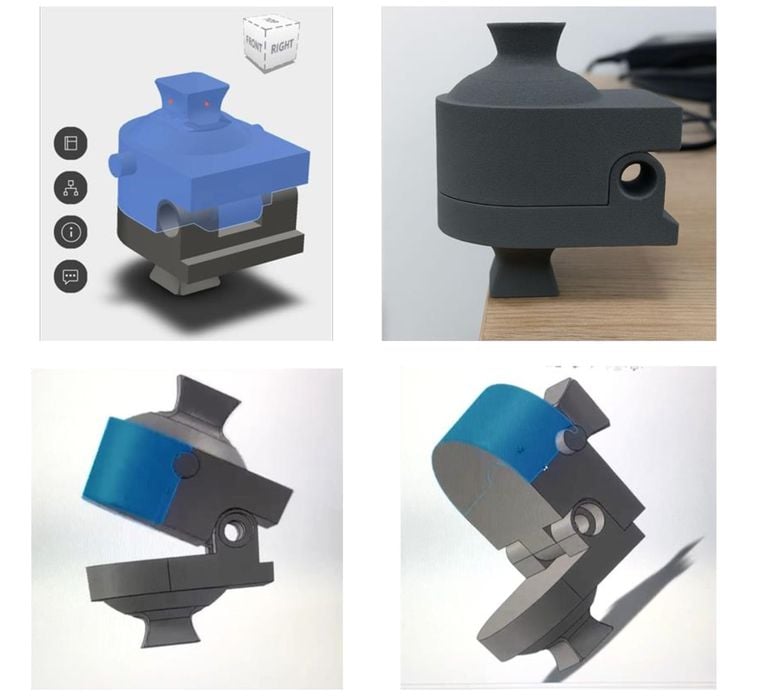

A research paper describes the “Pedi-knee”, a 3D printed prototype of a pediatric knee joint.

A Drexel-led team showed that porous PAEK knee revision topologies can be 3D printed using the FFF process strong enough for demanding loads.